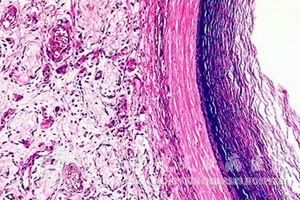

通常当患者发生鞍区表皮囊肿之后,其主要的症状表现就是进行性的视力、视野损害,在该症发展到了晚期后,则可出现视神经萎缩的情况,少数可出现内分泌障碍,还有少数病例可导致性功能障碍的。

对于该症的临床诊断通常需要找到以下的一些依据:

1.该症通常都会伴随很长的病史,病情的发展一般也比较缓慢;

2.该症的发生可能导致原发性视神经萎缩、双颞侧偏盲等视交叉压迫的症状表现产生;

3.发生该症后,患者的垂体功能一般还是正常的;

4.患者的颅骨平片蝶鞍大小正常,只是会出现视神经孔、视交叉沟等的局限性破坏现象。